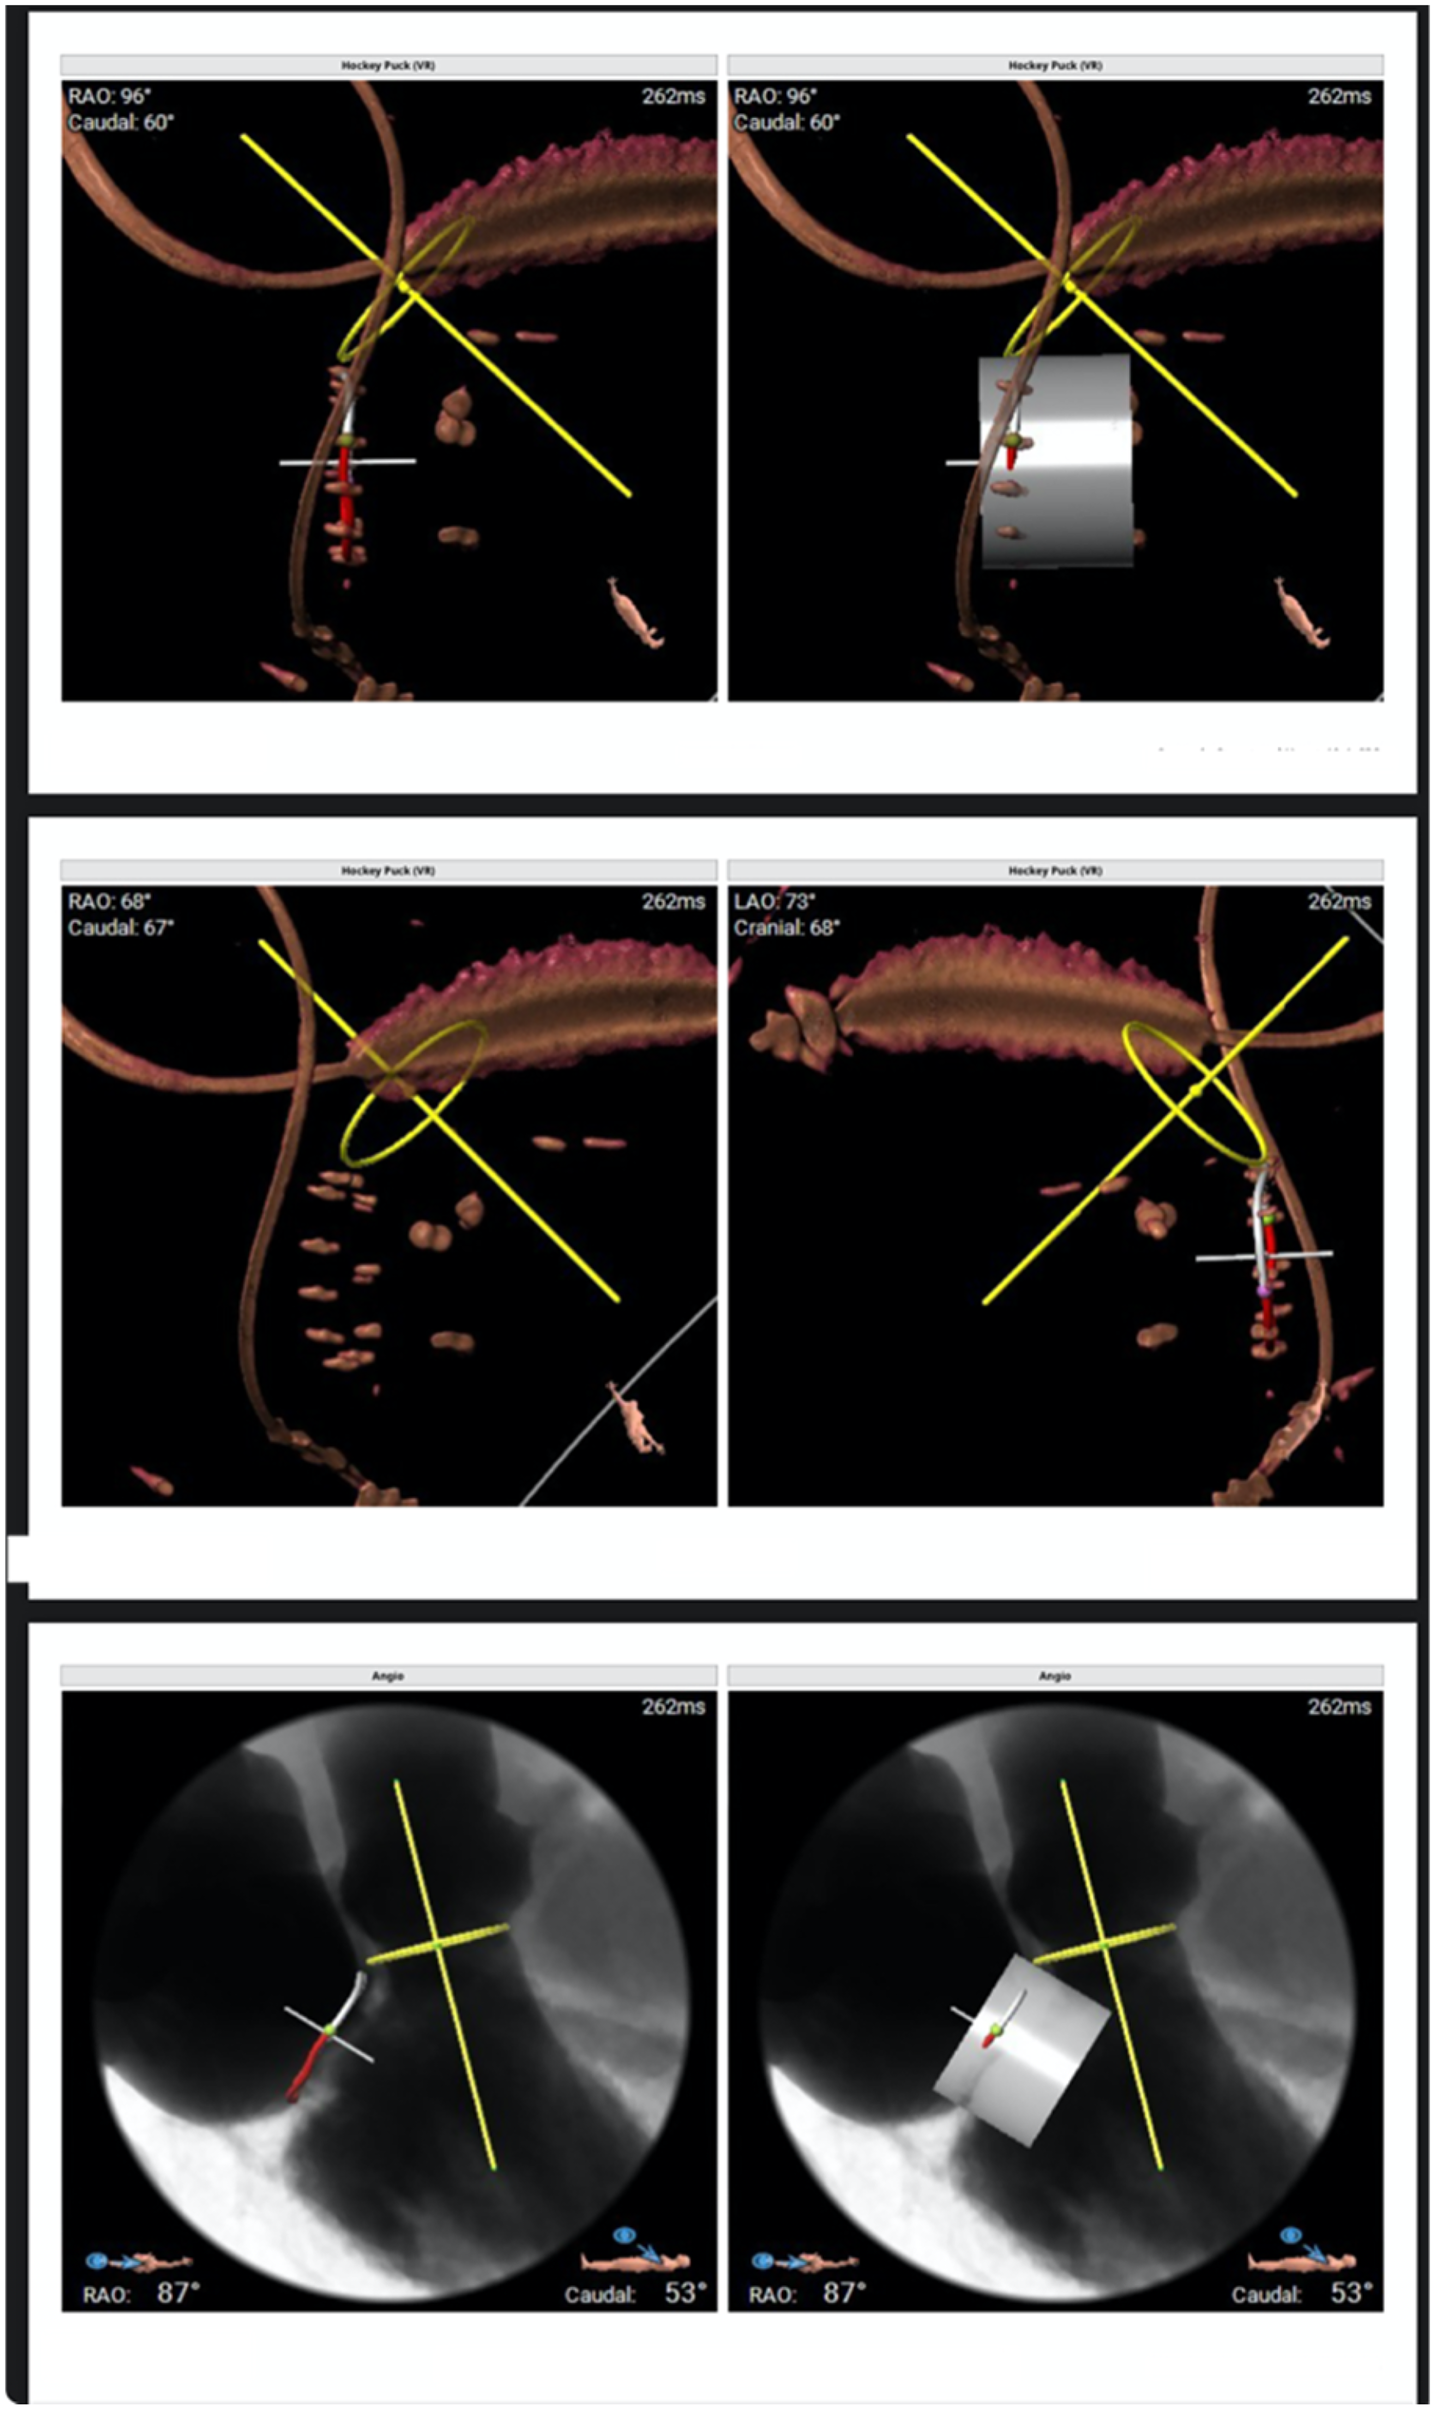

Figure 3

Three-dimensional volume-rendered reconstructions and multiplanar reformations are used to define the optimal fluoroscopic projections (“hockey puck” views) and to assess device coaxiality relative to the mitral annular plane.